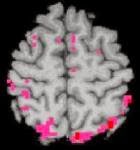

-az ideg- és agysejtek elhalnak-maradandó agykárosodás, pl. agyzsugorodás következik be